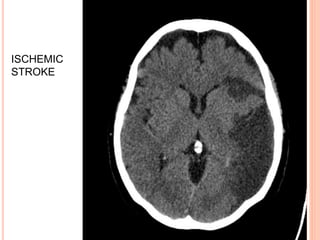

CT SCAN

 Mandatory initial investigation

 Haemorrhage appears instantly as a hyperdense

area

 Infarct appears as a hypodense area

 Infarct may not appear before 48 hrs

 MRI may be done instead but ct scan is more

sensitive for detecting haemorrhage

 Diffusion weighted MRI is good for identifying

ischaemic lesion.

ISCHEMIC

STROKE